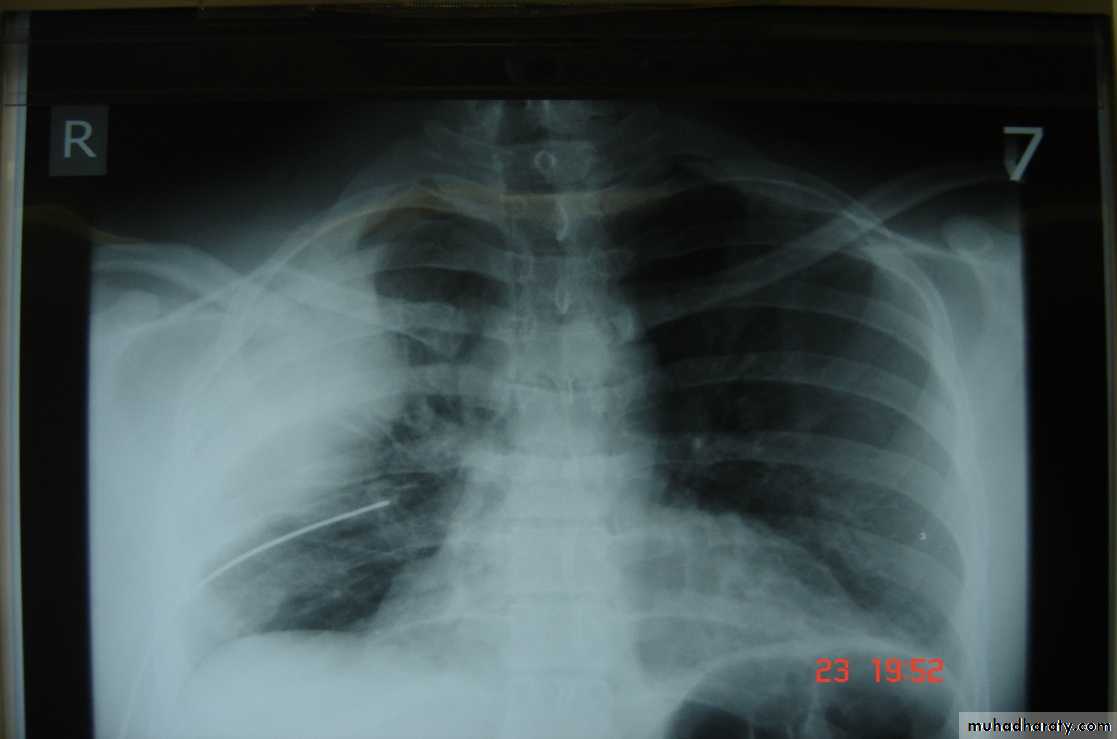

• 4-Pulmonary injuriesTrauma can lead to pulmonary contusion with interstitial edema which may lead to consolidation of the lung tissues and can be manage by antibiotics administration and clearing of secretion